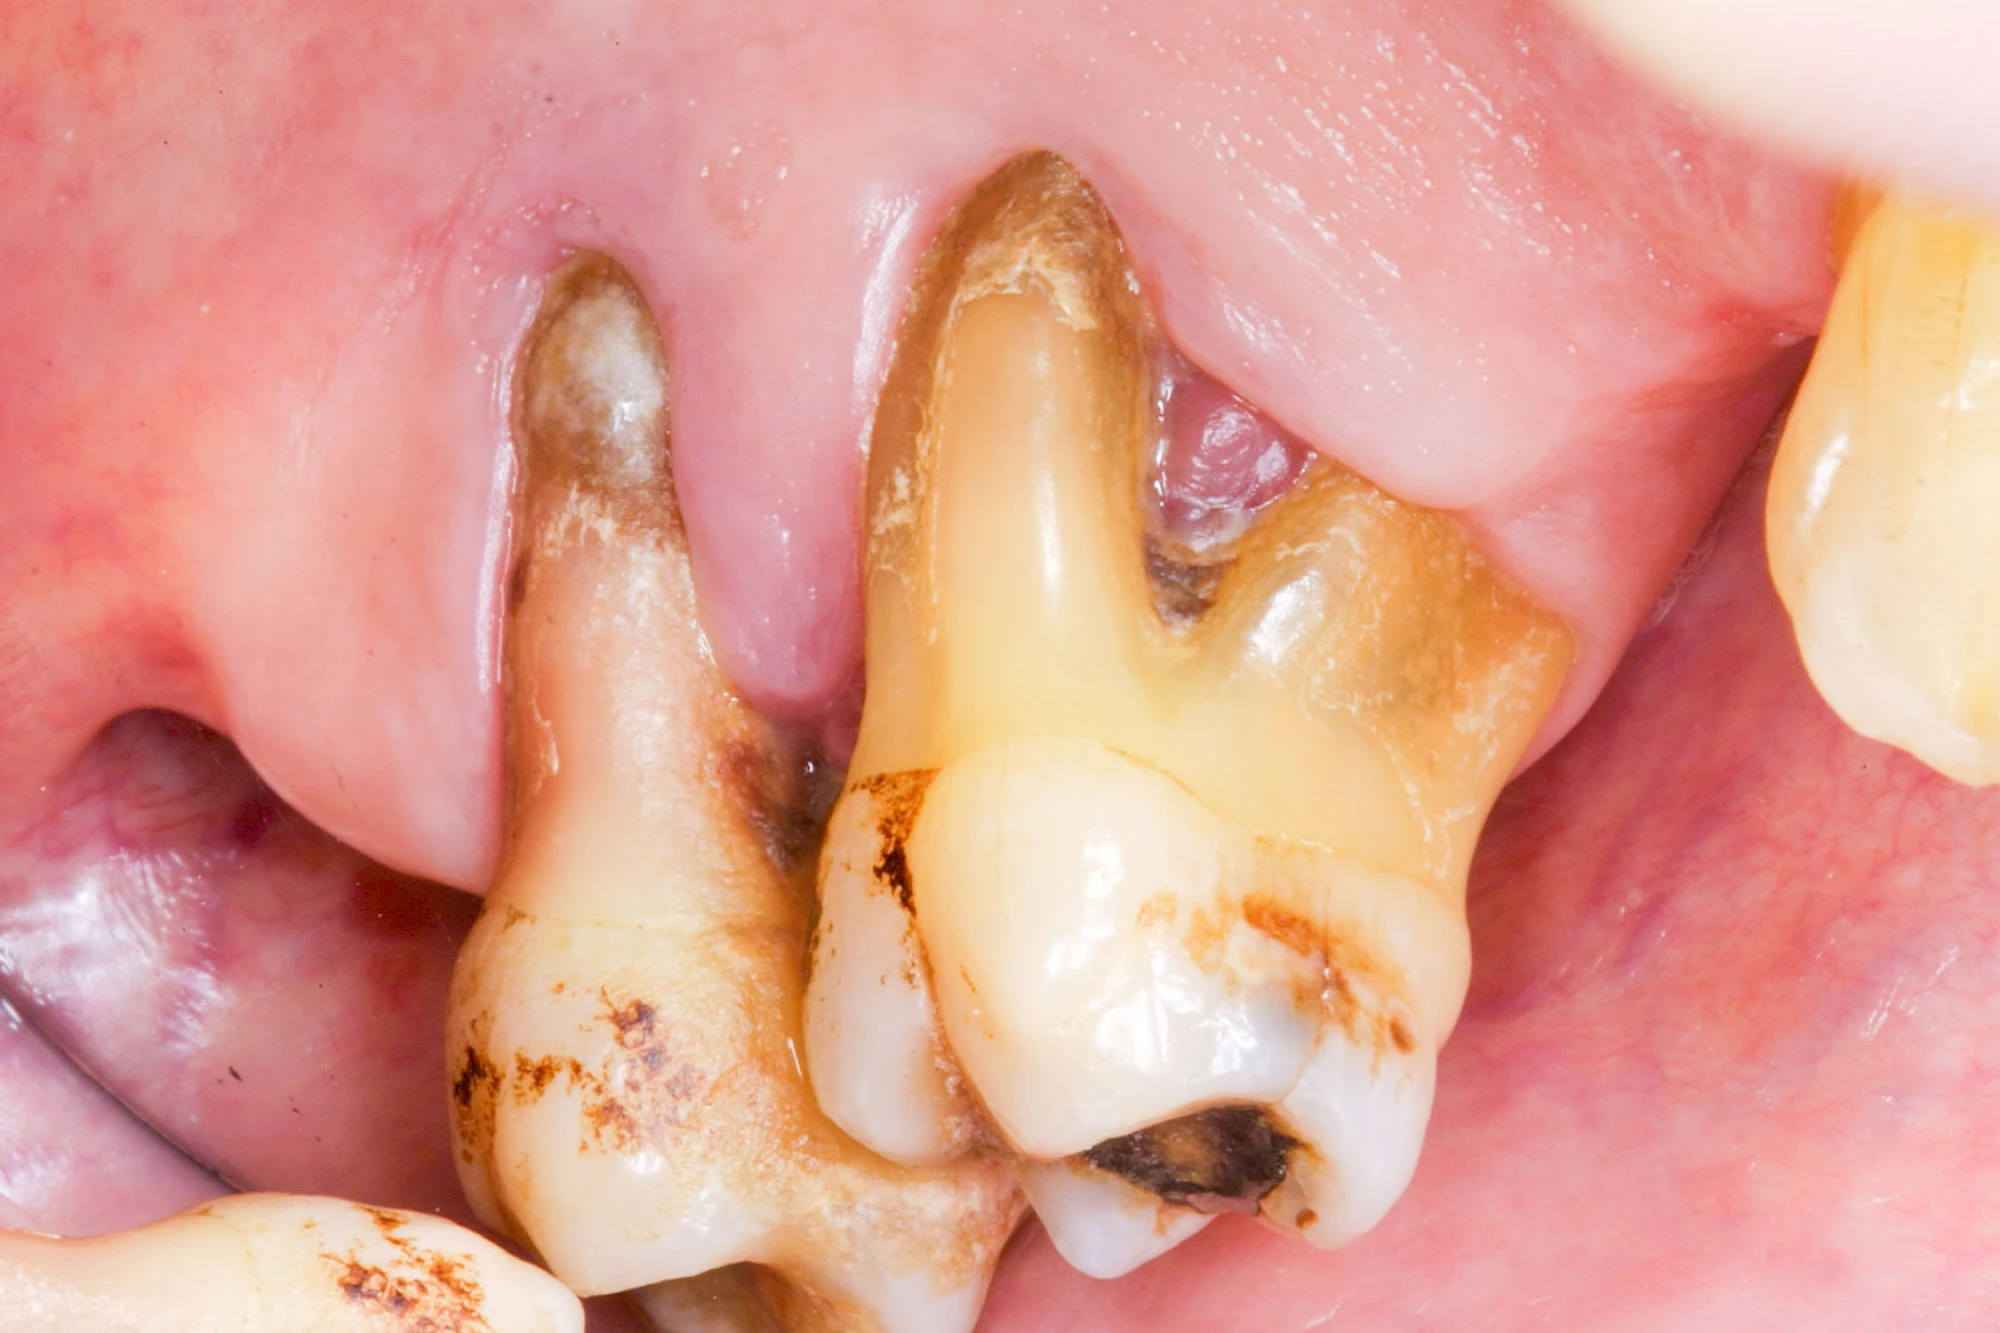

Ist zunächst nur das Zahnfleisch von der Entzündung betroffen, spricht man von Gingivitis. Später, wenn auch der Knochen um die Zähne herum entzündet ist, spricht man von einer Parodontitis. Bei der Parodontitis wird der Knochen nach und nach abgebaut und das Zahnfleisch zieht sich zurück. Die Zahnhälse und Zahnwurzeloberflächen liegen mehr und mehr frei. Die Zähne werden zunehmend lockerer und fallen schließlich aus.